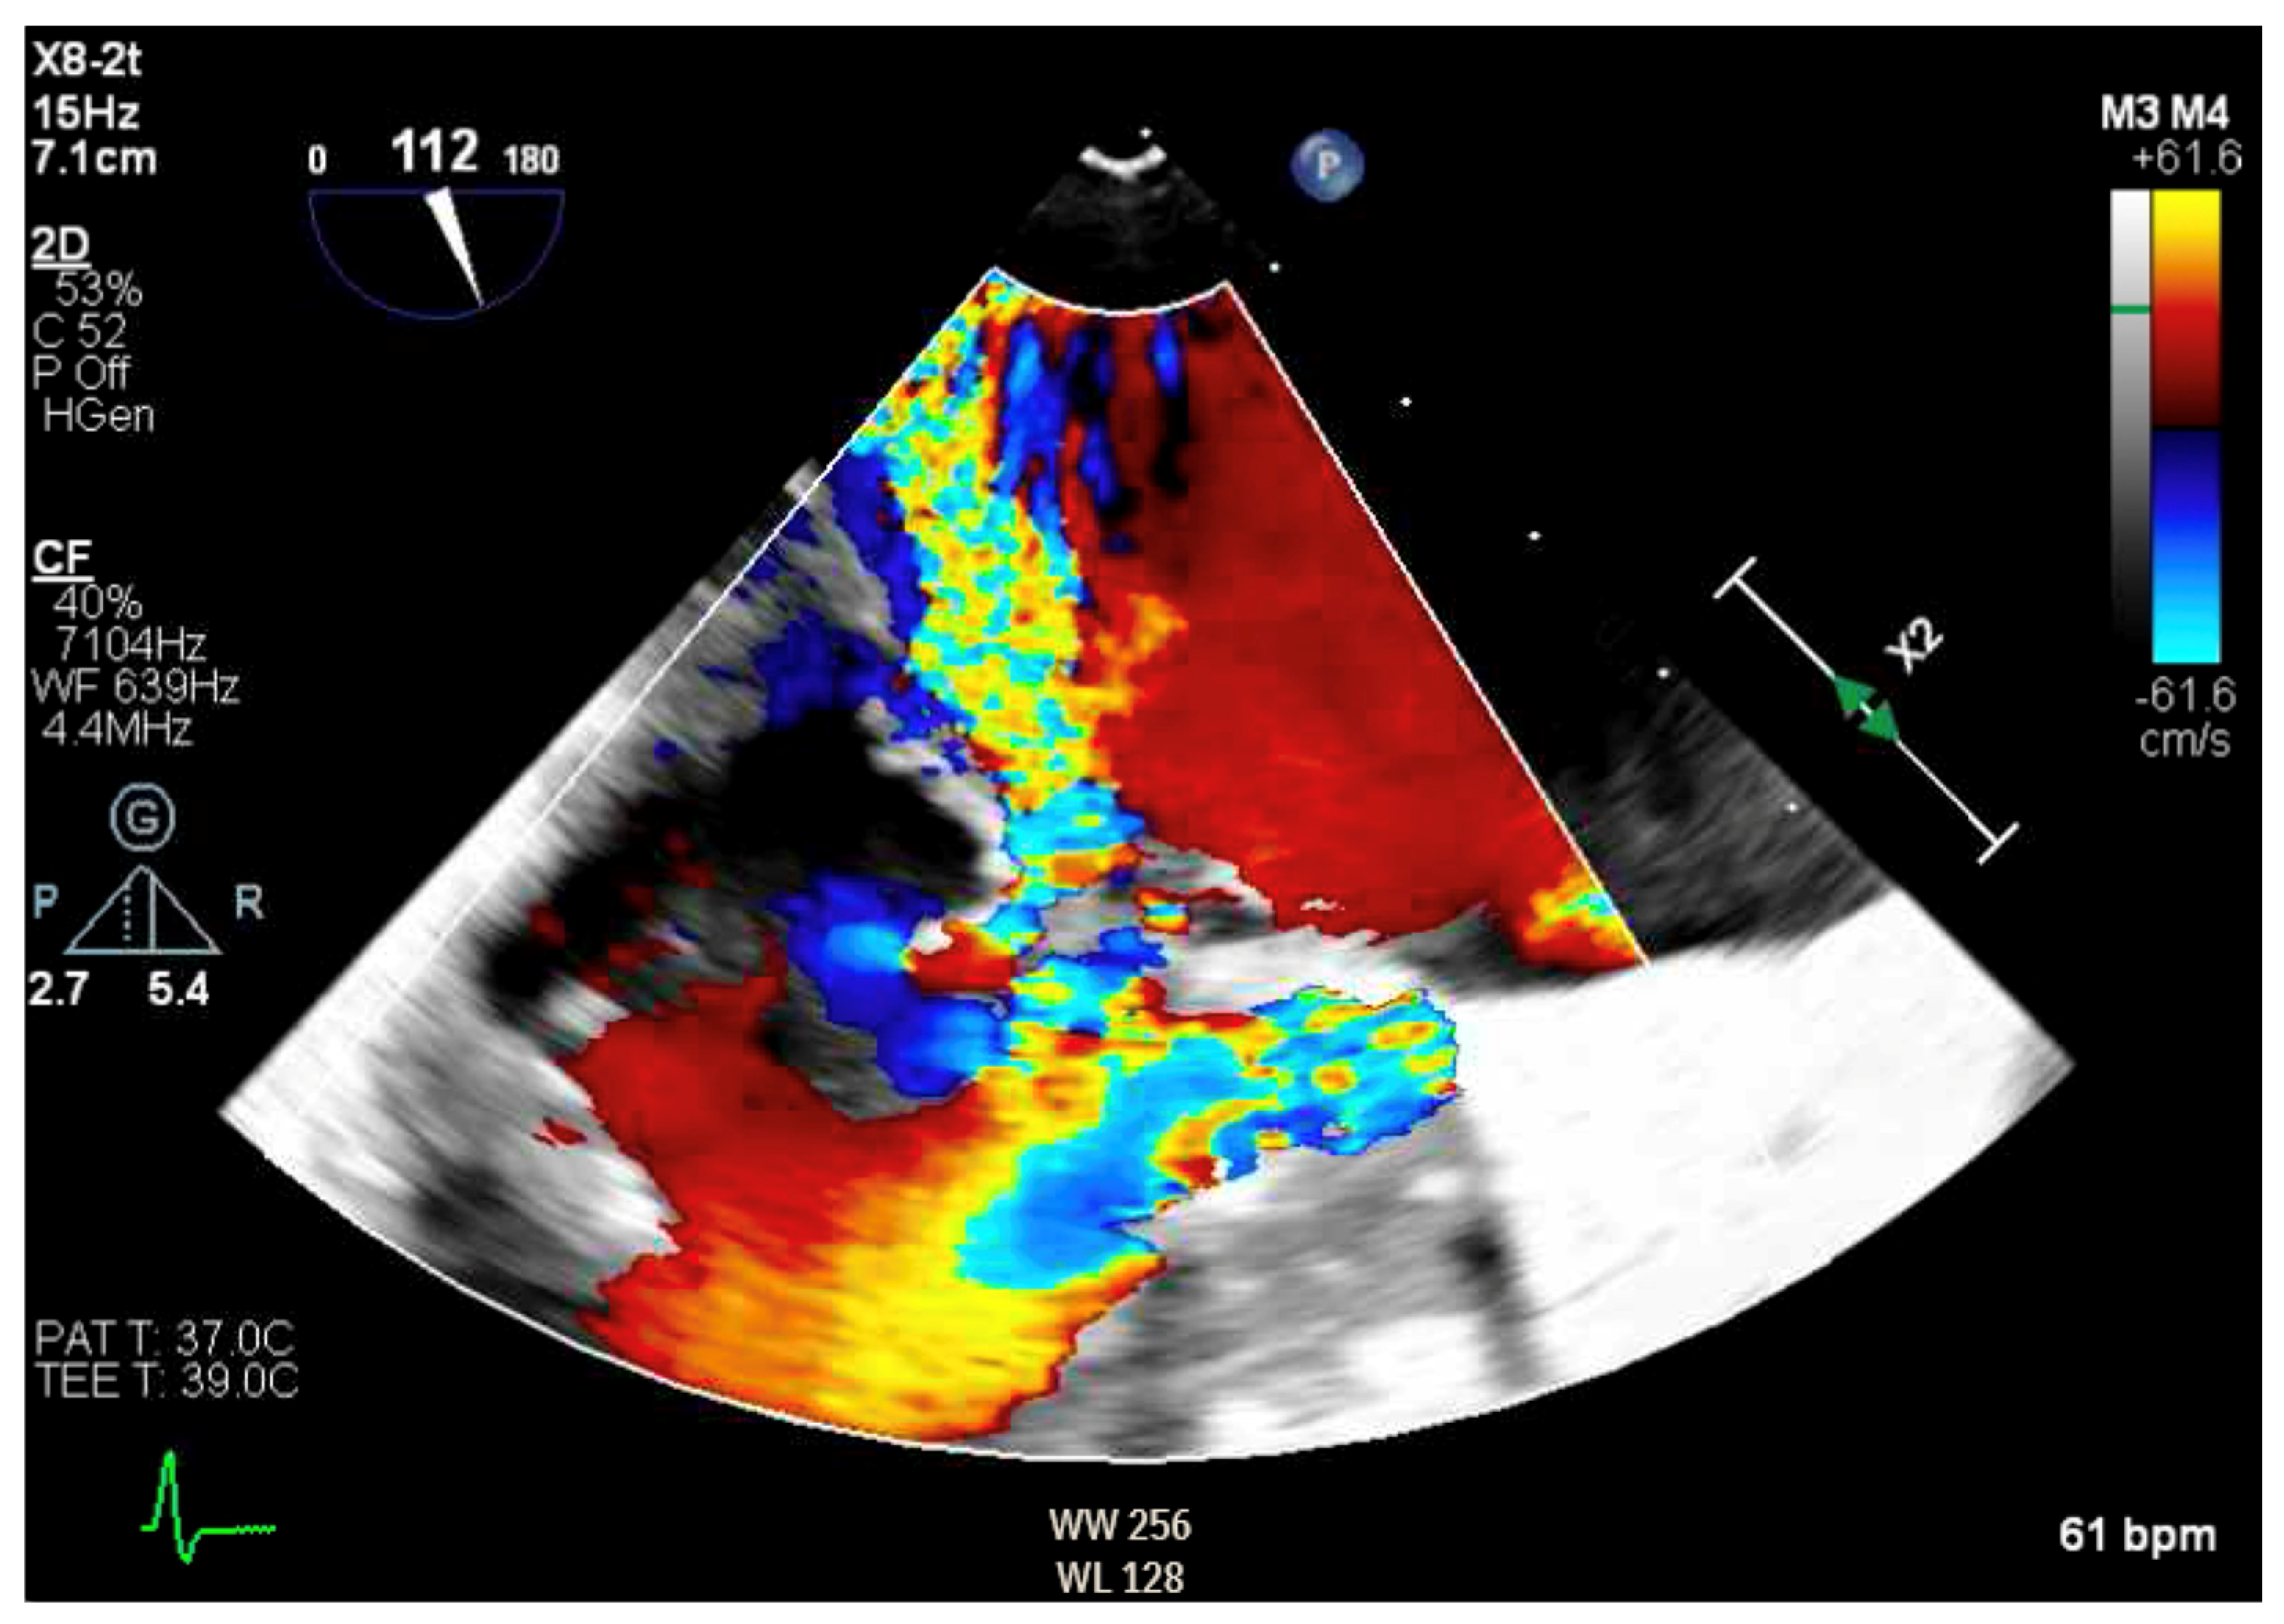

Figure 6.

Three-dimensional reconstruction of mitral valve showing anterior leaflet prolapse and flail.

Given the concern for primary MR, a transesophageal echocardiogram (TEE) was performed for further assessment. The study showed prolapse, chordal rupture and partial flail of the A3 leaflet with an area of non-coaptation and severe MR (Figure 6, Supplementary Video S4). Quantification using the proximal isovelocity surface area method revealed an effective orifice area of 0.46 cm2 and a regurgitant volume of 80 milliliters with notable systolic pulmonary vein flow reversal, consistent with severe Carpentier class II MR from prolapse and flail (Figure 7, Supplementary Video S5) [2]. This highlights the role of TEE and 3D imaging in assessing for SAM-independent causes of primary MR in patients with HCM. A TTE alone can miss these anatomical findings, especially in medial (A3 or P3) or lateral (A1 or P1) mitral scallops.